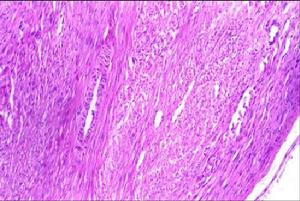

海綿狀血管瘤:最常見一般所謂的肝血管瘤就是指海綿狀血管瘤切面呈蜂窩狀,內充滿血液。光鏡下可見大小不等的囊狀血竇,血竇壁內襯覆一層內皮細胞血竇內常充滿紅細胞,有時有血栓形成,血竇之間為纖維組織所分隔,偶見有被壓縮的細胞索大的纖維分隔內有血管和小膽管,纖維分隔和管腔可發生鈣化或靜脈石形成瘤體周圍常有一層纖維包膜與正常肝組織分界。